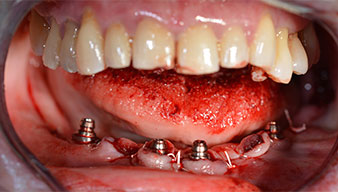

After removal of the residual dentition in the mandible, the alveolar crest was exposed from 37 to 47.

The mental foramen was first identified as a limiting anatomical structure and then the cortical bone of the crest was smoothed with the straight handpiece and a large rose-head bur (Fig. 4).

Angled abutments (35°) were screwed in to compensate for the divergence of the distal implants, with the result that the emergence profile of all implants was as perpendicular as possible to the bite plane. This is a prerequisite for occlusal placement of the provisional and subsequently the permanent denture (Fig. 15 and 16).